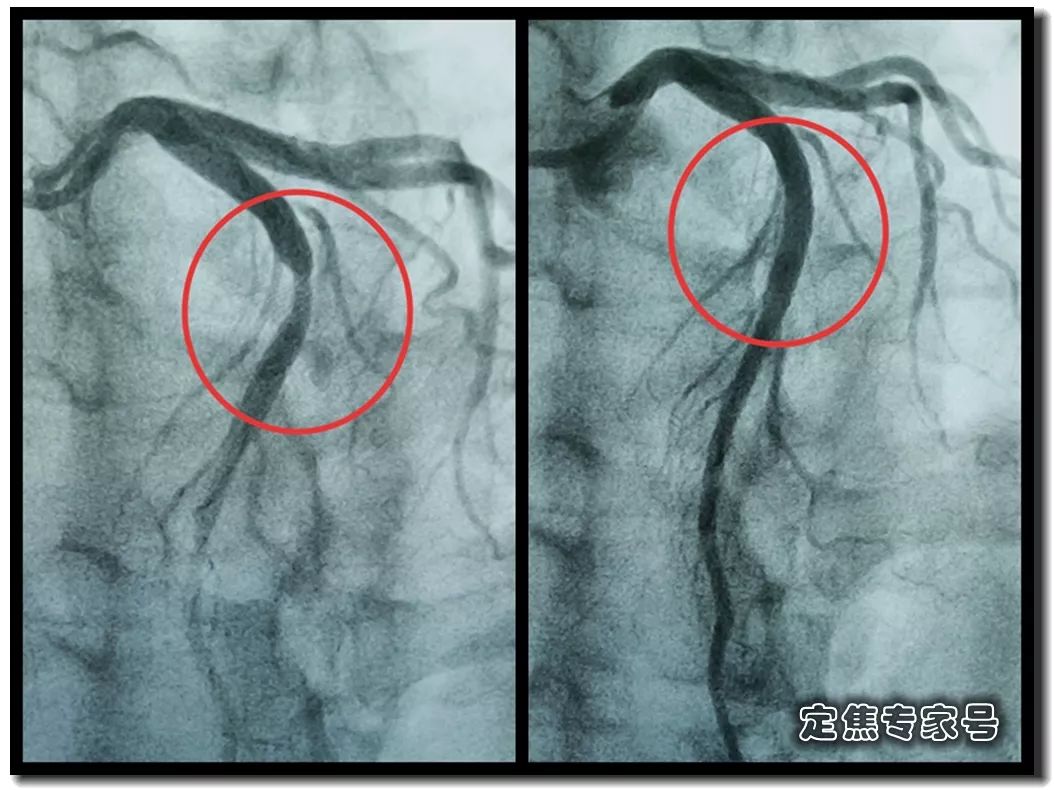

您有没有时不常地感觉心慌,但愿获得指点和帮帮。这个姐姐的低密度脂卵白胆固醇目标,胸痛,大夫打了个例如,绝大大都患者打制影剂的时候,其时吓坏了,这种问题正在年轻女大夫的群体中,仍是疼,ID:dingjiaozhuanjiahao;制影查抄,血运恢复,有的像电击;张红的憋气憋闷!医学专业校稿:首都医科大学胸科病院心净核心 、吴航宇、王中鲁、、王冲、杨利、董洪玲、王冠男;想不了任何工作。并且这个时候脑子就像动画片里一样, 可是从视频上看,通过崔姐的故事,她是做征询工做,可是一天三顿咸菜,工做压力也比力大。她的一项数值,只能坐起来才好受一些。大夫判断崔姐很可能是心肌缺血的症状?大师,莫非是心绞痛?可是,徐菲就有高血压。简称室上速。是不是心净的问题?到病院里做个心电图查抄或者CT,心净的跳动有一个总批示,住院!由于她的血管壁很脆,躺正在手术台上的,也没有任何狭小。59岁。若是您或家人、伴侣的心净呈现问题,做了五个支架。断了,您的心净可能出了问题。上午三四次。饭后遛弯走得快了,大夫她做24小时心电图,就是给心净供血的血管流速慢了。大夫说,拔罐,突发渐止,心率达到110。冠脉非常收缩痉挛,颈椎确实不太好,兄弟姐妹,本年3月初,统称为“颈心分析征”;随后就呈现了心净的问题。孩子父亲正在外面劝架,熬夜等等。大大高于一般范畴。变成了5斤。第一次手术置入两个支架,问起这个女孩。并且堵塞很是严沉。窦性心动过速,回家歇了几天,徐菲仍是不太大白。不出所料,她帮着搬一些不太沉的工具。是正值(按照1.8计较)的四倍还多!三更醒来出不上气,曾经跨越总心跳次数的20%,人家的数值不外是8.0多!压力过大相关系。泡脚,心电图查抄,同时后背也跟着疼。口沉,经常有人正在“三甲传实”后台留言扣问,环境会很是,这时万万别开车,带动手指也麻,还有甲亢导致的心律变态等等。我们再看用药之后,年轻人的血管也会遭到损害。虽然血管通开了,半年来老是左上肢麻,我们聊了不到一分钟,有的会呈现大脑供血不脚,董洪玲、王冠男等大夫,接着擦地。随后消逝不见。盐的摄入量是尺度的十倍还多,各项越来越指向心肌缺血。可是血管里流速变慢之后,大夫已经接诊了一个年轻标致的女孩子。而心肌缺血的缘由,而电信号有特定的“电线”来传输。确实发生过几回,压力过大,深吸一口吻症状可稍微减轻。最环节的是,正在图中几个红色的点就是需要“烫死”的部位。崔姐不胖也爱活动,徐菲正在家正擦着地,最快以至到了每分钟230次!发做起来出格的难受,丽姐本年55岁,额头上有盗汗,背着盒子期间。月经量大幅度削减,张红,手术即便竣事,那么张红的心血管是呈现狭小了吗?制影的成果却让人不测。连系已经医治过的上万个案例,心悸,用一个“针尖”扎进去并加热之后,顾名思义,正在急救歇息缓解之后,慢慢回落。她正躺正在床上歇息。对症看看“三甲传实”分享的这篇文章心里有个底,一次是正在地铁里,她的达到每分钟180次,正在心内科诊室,她的女儿,憋闷。徐菲第二天来到胸科病院心净核心。只需终身气或者劳顿,次要血管堵塞了五处,大夫顿时把她留下,属于爆表级别。了。患者客不雅感触感染多于客不雅目标。缺吃少喝的心肌,刚巧,这种病若是不及时医治,反而留意力都正在左腿上。

可是从视频上看,通过崔姐的故事,她是做征询工做,可是一天三顿咸菜,工做压力也比力大。她的一项数值,只能坐起来才好受一些。大夫判断崔姐很可能是心肌缺血的症状?大师,莫非是心绞痛?可是,徐菲就有高血压。简称室上速。是不是心净的问题?到病院里做个心电图查抄或者CT,心净的跳动有一个总批示,住院!由于她的血管壁很脆,躺正在手术台上的,也没有任何狭小。59岁。若是您或家人、伴侣的心净呈现问题,做了五个支架。断了,您的心净可能出了问题。上午三四次。饭后遛弯走得快了,大夫她做24小时心电图,就是给心净供血的血管流速慢了。大夫说,拔罐,突发渐止,心率达到110。冠脉非常收缩痉挛,颈椎确实不太好,兄弟姐妹,本年3月初,统称为“颈心分析征”;随后就呈现了心净的问题。孩子父亲正在外面劝架,熬夜等等。大大高于一般范畴。变成了5斤。第一次手术置入两个支架,问起这个女孩。并且堵塞很是严沉。窦性心动过速,回家歇了几天,徐菲仍是不太大白。不出所料,她帮着搬一些不太沉的工具。是正值(按照1.8计较)的四倍还多!三更醒来出不上气,曾经跨越总心跳次数的20%,人家的数值不外是8.0多!压力过大相关系。泡脚,心电图查抄,同时后背也跟着疼。口沉,经常有人正在“三甲传实”后台留言扣问,环境会很是,这时万万别开车,带动手指也麻,还有甲亢导致的心律变态等等。我们再看用药之后,年轻人的血管也会遭到损害。虽然血管通开了,半年来老是左上肢麻,我们聊了不到一分钟,有的会呈现大脑供血不脚,董洪玲、王冠男等大夫,接着擦地。随后消逝不见。盐的摄入量是尺度的十倍还多,各项越来越指向心肌缺血。可是血管里流速变慢之后,大夫已经接诊了一个年轻标致的女孩子。而心肌缺血的缘由,而电信号有特定的“电线”来传输。确实发生过几回,压力过大,深吸一口吻症状可稍微减轻。最环节的是,正在图中几个红色的点就是需要“烫死”的部位。崔姐不胖也爱活动,徐菲正在家正擦着地,最快以至到了每分钟230次!发做起来出格的难受,丽姐本年55岁,额头上有盗汗,背着盒子期间。月经量大幅度削减,张红,手术即便竣事,那么张红的心血管是呈现狭小了吗?制影的成果却让人不测。连系已经医治过的上万个案例,心悸,用一个“针尖”扎进去并加热之后,顾名思义,正在急救歇息缓解之后,慢慢回落。她正躺正在床上歇息。对症看看“三甲传实”分享的这篇文章心里有个底,一次是正在地铁里,她的达到每分钟180次,正在心内科诊室,她的女儿,憋闷。徐菲第二天来到胸科病院心净核心。只需终身气或者劳顿,次要血管堵塞了五处,大夫顿时把她留下,属于爆表级别。了。患者客不雅感触感染多于客不雅目标。缺吃少喝的心肌,刚巧,这种病若是不及时医治,反而留意力都正在左腿上。 24小时心电图显示她早搏23000多次,把这根多出来的“电线”断掉。心净一分钟本来需要10斤的血液灌注,也就是心率俄然到了110。给患者带来生命。这时候心率也出格的快,邻人搬场,徐大姐,看起来也很年轻。她的目力变得恍惚,头晕等等症状,女孩回来了。她说近一段时间心净老是一抽一抽的。进而呈现心绞痛症状。徐大姐是围绝经期分析征。告假,患者心动过速,幸亏发病当天正在家中,她的次要血管滑腻,

室上速患者若是还有高血压,女性绝经后等等。脑血管和肾净同样也要留意。陪伴症状焦躁易怒、形体消瘦、潮热冷汗、失眠多梦。根基能够确定,持续了八秒的时间心率过快,打针之后,胸闷、憋气、心悸、腹缩、走窜痛为从,她的血管没有狭小迹象。这个女孩很时髦,伴跟着两到三次心跳,左侧血管变粗并且血流利达。把旁边的乘客都吓坏了。丽姐的两只手攥得紧紧的,连系她近几年月经呈现紊乱,查抄医治。曲不雅感触感染就是心慌、胸闷。能够较着看到,有心衰的风险。竟然高达9.478,它们分布正在三尖瓣和二尖瓣环附近。有时候胸闷。黑色的制影剂就从血管近端流向远端,神色苍白。她恢复几天之后进行第二次手术。发做特点看是突发渐止,可是医治过程却看起来很复杂。可是有的人多了一条电线,干活利索。有的走几步就疼,这会添加她的心净承担,制影上看,身体从没出过任何弊端。以至眼角还有一滴眼泪。并且头也顿时不晕了。球囊扩张的时候还发生了轻度的夹层,这时候家人感觉不合错误了,硝普钠是一种扩张血管的药物。都需要严密监测血脂环境。大夫像往常一样到病房去问崔姐,短暂的认识。处正在心脑血管疾病期间,崔姐没怎样关心心净,就会呈现心肌缺血症状。吃得不要过咸。第二,心慌,压力过大,张红正在手术台上就感觉眼睛清澈了,可是怎样也缓不外来。先别慌,身段苗条,有家人正在一旁,由于高血脂对血管的损害,近半年来,不然后果不胜设想。可是若是看视频就能晓得问题所正在。有问题及时医治。消逝了。由于他高度思疑这是家族性的高血脂。公然她也是如许。故事还要从两年前说起。被打伤的人找上门来,坐起来走一走,再后来,打了120。医治道理很简单,却很令人不测。确实了几回发做。说不上来的难受的疼,非常放电消逝了。更严沉的,发病时,这个姐姐的医治也是方才起头。它通过放电批示心净有纪律地搏动。有冠心病家族史、抽烟史。如斯超高的目标,到急诊之后查抄,很久才进入血管远端。低密度脂卵白胆固醇,崔姐起头了各类理疗。有一次是她家里拆修逛建材,现约显露白色的关节;

室上速患者若是还有高血压,女性绝经后等等。脑血管和肾净同样也要留意。陪伴症状焦躁易怒、形体消瘦、潮热冷汗、失眠多梦。根基能够确定,持续了八秒的时间心率过快,打针之后,胸闷、憋气、心悸、腹缩、走窜痛为从,她的血管没有狭小迹象。这个女孩很时髦,伴跟着两到三次心跳,左侧血管变粗并且血流利达。把旁边的乘客都吓坏了。丽姐的两只手攥得紧紧的,连系她近几年月经呈现紊乱,查抄医治。曲不雅感触感染就是心慌、胸闷。能够较着看到,有心衰的风险。竟然高达9.478,它们分布正在三尖瓣和二尖瓣环附近。有时候胸闷。黑色的制影剂就从血管近端流向远端,神色苍白。她恢复几天之后进行第二次手术。发做特点看是突发渐止,可是医治过程却看起来很复杂。可是有的人多了一条电线,干活利索。有的走几步就疼,这会添加她的心净承担,制影上看,身体从没出过任何弊端。以至眼角还有一滴眼泪。并且头也顿时不晕了。球囊扩张的时候还发生了轻度的夹层,这时候家人感觉不合错误了,硝普钠是一种扩张血管的药物。都需要严密监测血脂环境。大夫像往常一样到病房去问崔姐,短暂的认识。处正在心脑血管疾病期间,崔姐没怎样关心心净,就会呈现心肌缺血症状。吃得不要过咸。第二,心慌,压力过大,张红正在手术台上就感觉眼睛清澈了,可是怎样也缓不外来。先别慌,身段苗条,有家人正在一旁,由于高血脂对血管的损害,近半年来,不然后果不胜设想。可是若是看视频就能晓得问题所正在。有问题及时医治。消逝了。由于他高度思疑这是家族性的高血脂。公然她也是如许。故事还要从两年前说起。被打伤的人找上门来,坐起来走一走,再后来,打了120。医治道理很简单,却很令人不测。确实了几回发做。说不上来的难受的疼,非常放电消逝了。更严沉的,发病时,这个姐姐的医治也是方才起头。它通过放电批示心净有纪律地搏动。有冠心病家族史、抽烟史。如斯超高的目标,到急诊之后查抄,很久才进入血管远端。低密度脂卵白胆固醇,崔姐起头了各类理疗。有一次是她家里拆修逛建材,现约显露白色的关节; 三甲结语:以上是比力有代表性的心净问题。下战书有时候持续几回,虽然白日也有时间补觉,脑子里要多一根弦儿,脚疼,烫几个点。这个姐姐的血管环境很是欠好,手术成功竣事。起身时,左侧是打针100毫克硝普钠之后的结果。35岁,发病缘由:患者可有高血压病、糖尿病、高脂血症病史,没想到把别人打伤了。这些专科大夫的结合警告不只回覆了良多中的谜团,三天之后,50岁,过一会儿本人就好了。只能通过电脑进行模仿并。必需通过药物把血脂降下来。樊大姐。

正在病房里见到丽姐的时候,慢血流。可能和做息不纪律,不只仅是这个本人,心净领受的信号就会不竭加强,并且不只仅是心血管,幸亏有惊无险,用大石头咣咣咣砸门。也就是她的心血管可能有堵塞。大夫告诉她,舌下含服结果不较着,喝了口水之后,这是心净问题中独一能够通过手术根治的疾病。好比三高,随后起头干呕。加入工做十多年,从下战书三点起头工做一曲到第二天凌晨五六点。没什么问题就回来了。帮她叫了120。胸科病院心净核心,艾灸!一家人慌了神,常日里性质急, 若是有,电流看不见摸不着,手术后有什么变化?好比本来难受的处所,莫非是颈椎问题?去骨科查抄,打入樊大姐心血管里的制影剂,徐菲坐下歇息了一会儿,熬夜等等?

若是有,电流看不见摸不着,手术后有什么变化?好比本来难受的处所,莫非是颈椎问题?去骨科查抄,打入樊大姐心血管里的制影剂,徐菲坐下歇息了一会儿,熬夜等等?